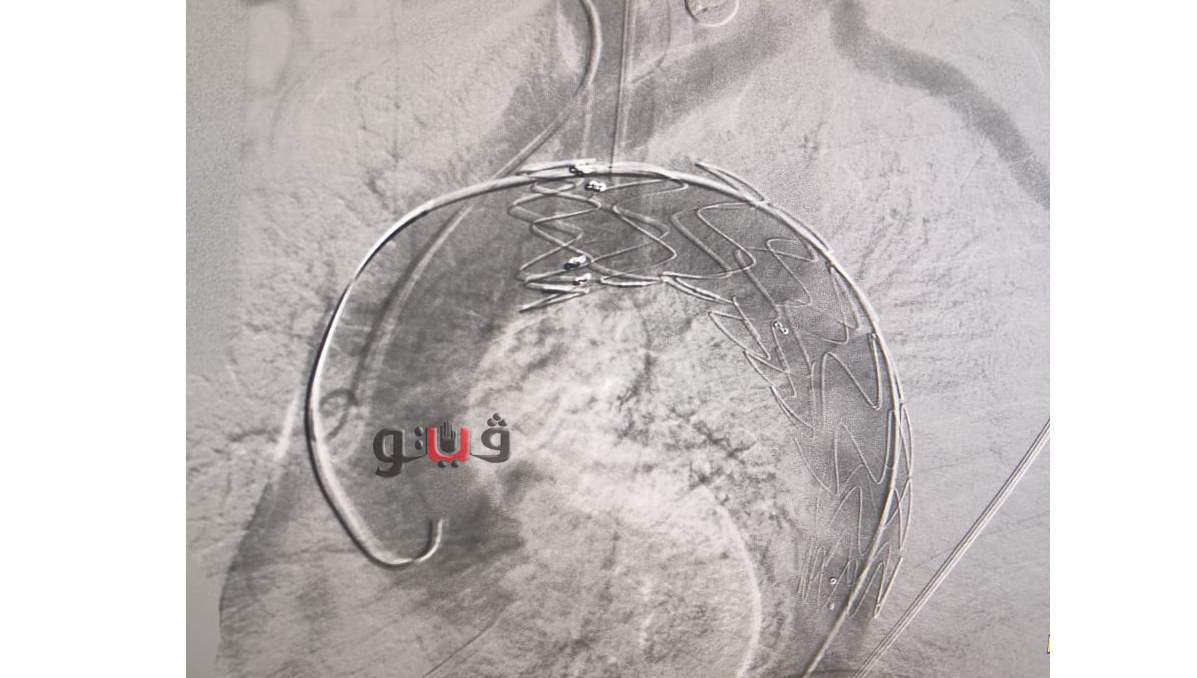

شهد مركز جراحة القلب وجراحة الاوعية الدموية بجامعة المنصورة في سابقة هي الاولى من نوعها إجراء أول حالة تيفار بقسطرة الهيبريد باستخدام تقنية الدعامات المغطاة.

وقام فريق من جراحي الأوعية الدموية برئاسة الدكتور مسعد سليمان مدير مركز جراحة الأوعية الدموية، وبحضور ممثلين لجراحي القلب وفريق العناية بإجراء قسطرة تداخلية لتصحيح انشطار بشريان الاورطي الصدري نتيجة الارتفاع المزمن بضغط المريض وأدي الانشطار الي تمدد بشريان الاورطي منذرا بحدوث انفجار علاوة علي توقف الدورة الدموية عن بعض الاعضاء الحيوية.

وتم توفير كافة المستلزمات والمتطلبات بواسطة إدراة العلاج ضمن قوائم الانتظار وتم اجراء التدخل بواسطة تقنية الدعامات المغطاه والتي تضمن اعادة سريان الدم في الشريان الاورطي الرئيسي .

واستغرقت ٤٥ دقيقه مع توفير كافة الاستعدادات من فريق جراحة القلب وكذلك من فريق التخدير برئاسة الدكتورة دعاء جلال وفريق العنايه المركزه برئاسه الدكتور محمد عادل واظهرت فحوصات المريض فور انتهاء الايفار بنجاح التدخل بنسبه ١٠٠٪ .

الجدير بالذكر ان هذا النوع من التدخلات يشمل عدد كبير من مرضي الضغط المرتفع كانوا لايجدوا سبيل لحلول جذرية لمنع حدوث مضاعفات علي المرضي مثل انفجار التمدد او امتداده الي شرايين الكلي او الامعاء او الاطراف ويمثل هذا النوع من التقنية تطور نوعي في الخدمة المقدمة بمركز جراحة الاوعية الدموية.